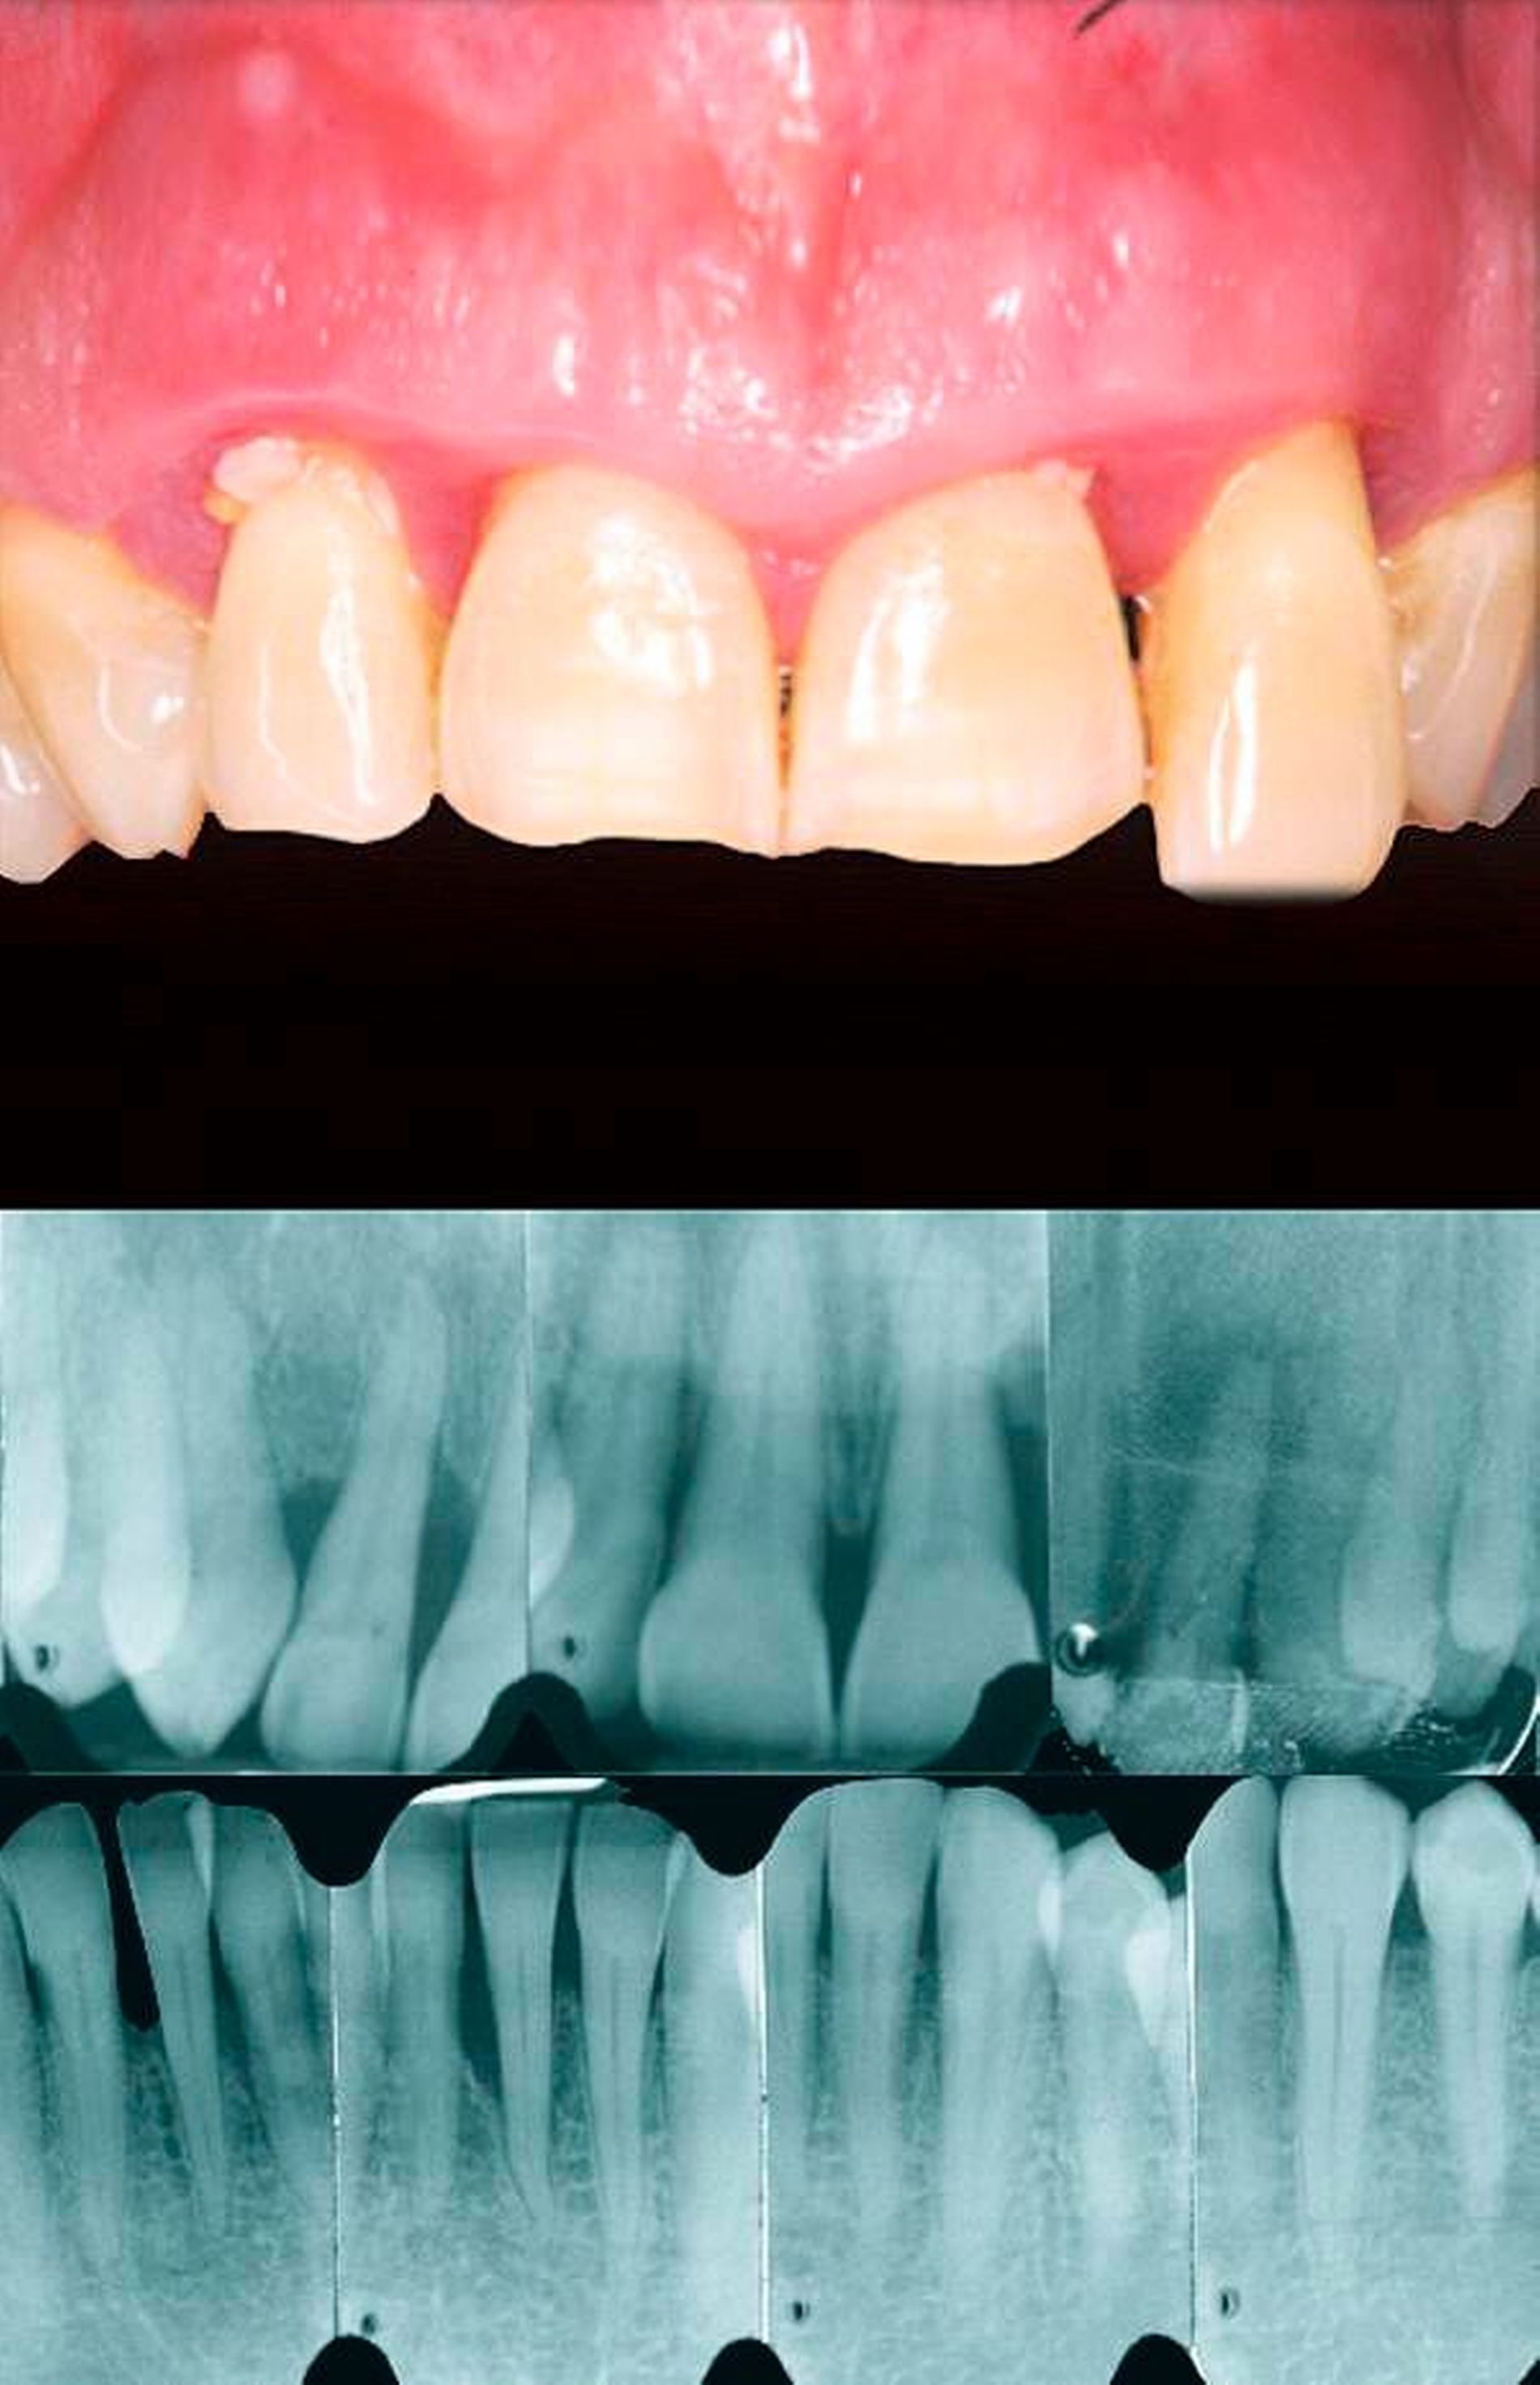

Das Hauptziel ist, den Schweregrad und das Ausmaß der durch Parodontitis zerstörten und geschädigten Gewebe zu klassifizieren. Dies geschieht durch die Messung des CAL mittels klinischer Sondierung und des Knochenabbaus durch radiologische Untersuchung. Diese Messungen müssen die Anzahl der Zähne, deren Verlust auf eine Parodontitis zurückzuführen ist, beinhalten.

Evidenz basiert auf der verfügbaren longitudinalen Beobachtung: zum Beispiel in der Form von älteren Röntgenaufnahmen in diagnostischer Qualität.

Indirekte

Evidenz basiert auf der Messung des Knochenabbaus des am stärksten betroffenen Zahnes im Gebiss als Funktion des Alters (gemessen als röntgenologischer Knochenabbau in Prozent der Wurzellänge dividiert durch das Alter des Patienten). Der Grad der Parodontitis kann dann durch das Vorhandensein von Risikofaktoren modifiziert werden.

Schritt 3a: Parodontitis-Fall, dessen Stadium festgelegt werden muss

Um das Stadium eines individuellen Parodontitis-Falles festzustellen, sind folgende Informationen erforderlich: vollständiger Röntgenstatus, ein Parodontalstatus und die parodontale Vorgeschichte des Zahnverlusts (periodontal history of tooth loss, PTL). Zuerst bewerten wir das Ausmaß der Erkrankung, indem beurteilt wird, ob CAL/BL weniger als 30 Prozent der Zähne (lokalisiert) oder 30 Prozent und mehr betrifft (generalisiert). Dann definieren wir das Stadium der Erkrankung, indem wir die Schwere (mit CAL, BL und PTL) und Komplexität (durch die Beurteilung von PPD, Furkations- und intraossären Läsionen, Zahnhypermobilität, sekundärem okklusalem Trauma, Bisskollaps, Zahnwanderung, Auffächern oder weniger als zehn okkludierende Zahnpaare) bestimmen.